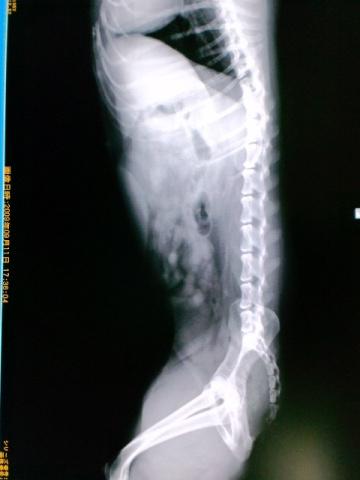

いつも体の中心で支えてくれてる腰の骨。骨盤、仙骨、椎間板。

私の背骨のゆがみと、姿勢の悪さから

腰1点に全体重がかかり、私の全てを抱え込んで仙骨は悲鳴をあげてましたね。